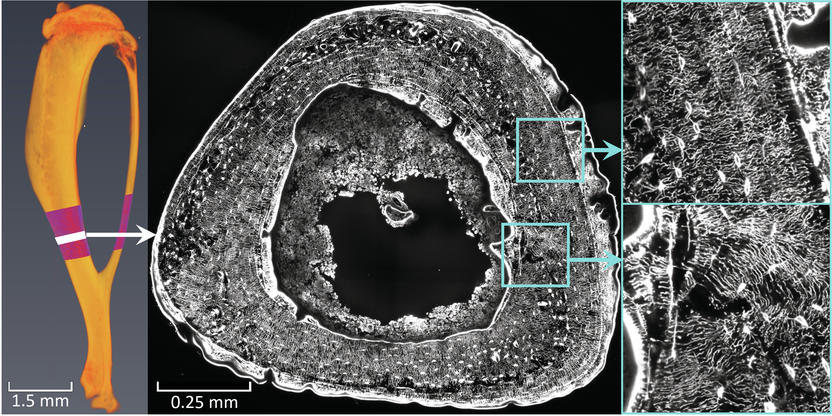

Bones can be trained like muscles. In the course of the study, researchers in Montreal examined mouse bones that had undergone controlled "bone training". In Potsdam, Weinkamer and his team used a scanning laser microscope to obtain 3D images of the cell network in the trained bones. The image data was used to analyze and evaluate networks with millions of canals by means of computer simulations that calculate the fluid flow through the network: "Based on our results, we are convinced that the bone cells within the networks can perceive the fluid flow, communicate with each other and thus pass on information such as 'need of bone growth' to other cells," says Alexander van Tol. He adds: "The examined mice reacted differently to bone training. A mouse that produced particularly little new bone has a network whose architecture allows only a slow flow of fluid". He adds: "We therefore believe that the same applies to humans: Bone can be strengthened particularly well through physical activity if the network structure within the bone 'plays along'. This study was the first to not only analyze the network architecture, but also to evaluate the quality of this architecture in terms of the perception of mechanical stimuli.